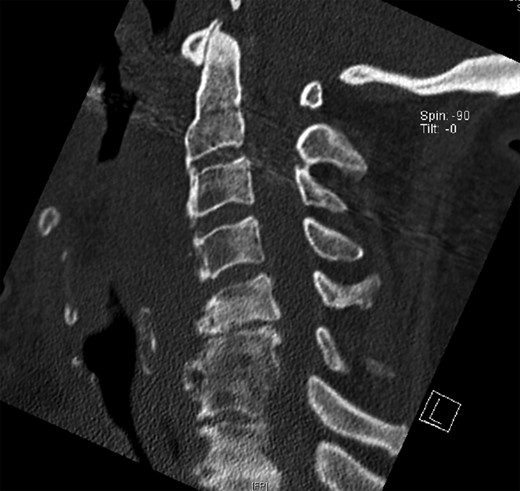

The X-ray and CT scan of the cervical spine revealed significant hyperostosis of the ventral cervical spine segments C3–C7. Hyperostosis was most extensive at segments C3–C5 causing stenosis of the pharyngeal lumen at the level of the larynx (Fig. 1). Due to accompanying joint pain, additional radiological examinations were performed. CT of the right shoulder showed extensive osseous proliferation of the medial humeral head reducing the articular space of the glenohumeral joint, as well as calcification of the rotator cuff (Fig. 2). In the left ankle, the CT scan revealed ossification of the deltoid ligament, and Kellgren grade 4 arthrosis of the tibiotalar and talocalcaneal joints (Fig. 3).

CT of the cervical spine in a sagittal view. Osteophytes of the ventral cervical spine segments C3–C5 protrude towards the oesophageal lumen.

Surgical access to the cervical spine through a right-sided standard anterolateral approach showed osseous vegetations, which were strongly attached to the ventral spine and caused ventral displacement of the oesophagus. There was no infiltration of neighbouring tissues. Hyperostotic tissue at levels C3–C5 was carefully removed. Within 24 h, a single-dose 6-MeV photon of 7 Gy was applied. Indometacin treatment was initiated with 50 mg twice daily. A control CT examination showed successful removal of hyperostosis from segments C3 to C5 with intact vertebrae and proper configuration of the cervical lordosis without signs of instability (Fig. 4).

CT of the cervical spine in a sagittal view. Osteophytes from C3 to C5 are removed. Sagittal alignment of the spine is preserved.